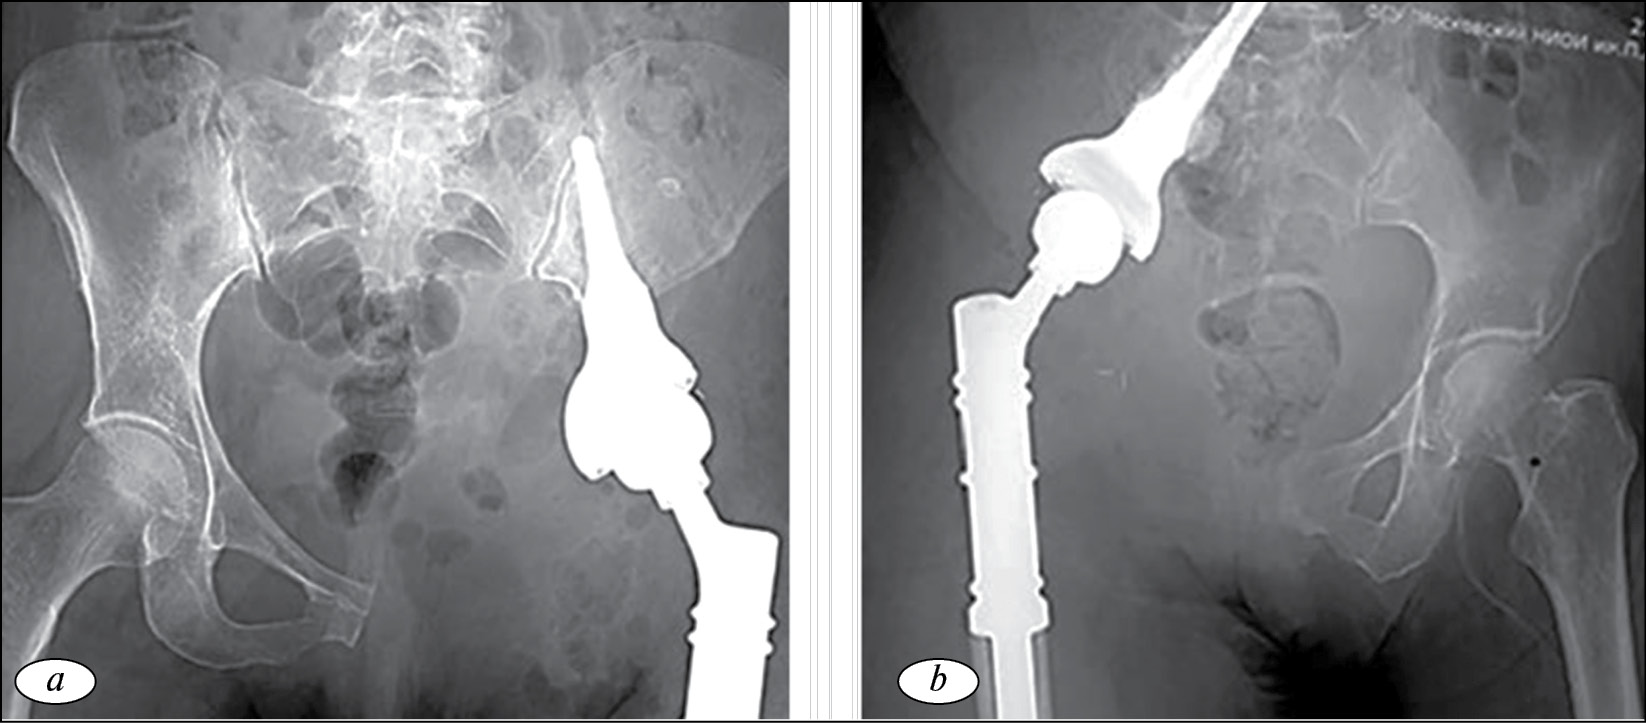

Реконструкция при помощи артродеза

Альтернативная методика реконструкции вертлужной впадины была предложена M.I. O’Connor и F. Sim в 1989 г. [19]. Опороспособность конечности после удаления опухоли восстанавливалась путем формирования различных типов артродеза проксимального отдела бедренной кости с подвздошной и лонной костями при помощи металло-остеосинтеза (рис. 2).

Рис. 2. Реконструкция вертлужной впадины при помощи артродеза проксимального отдела бедренной кости с подвздошной костью: a — cхема операции; b — рентгенограмма костей таза с подвздошно-бедренным накостным металлоостеосинтезом пластиной и артродезированием [19]

Авторы сообщает о 29 прооперированных больных с саркомами костей параацетабулярной области. Средний период наблюдения составил 66 мес. Прогрессирование заболевания диагностировано у 12 (40 %) прооперированных больных, при этом рецидив опухоли отмечен лишь у 2 (8 %) пациентов. Функциональный результат после операции оценен как хороший у 35 %, удовлетворительный у 25 % и неудовлетворительный у 40 % больных. Общее количество осложнений составило 62 %. Инфицирование послеоперационной раны было у 31 % и формирование ложного сустава области артродеза также у 31 % пациентов [19].